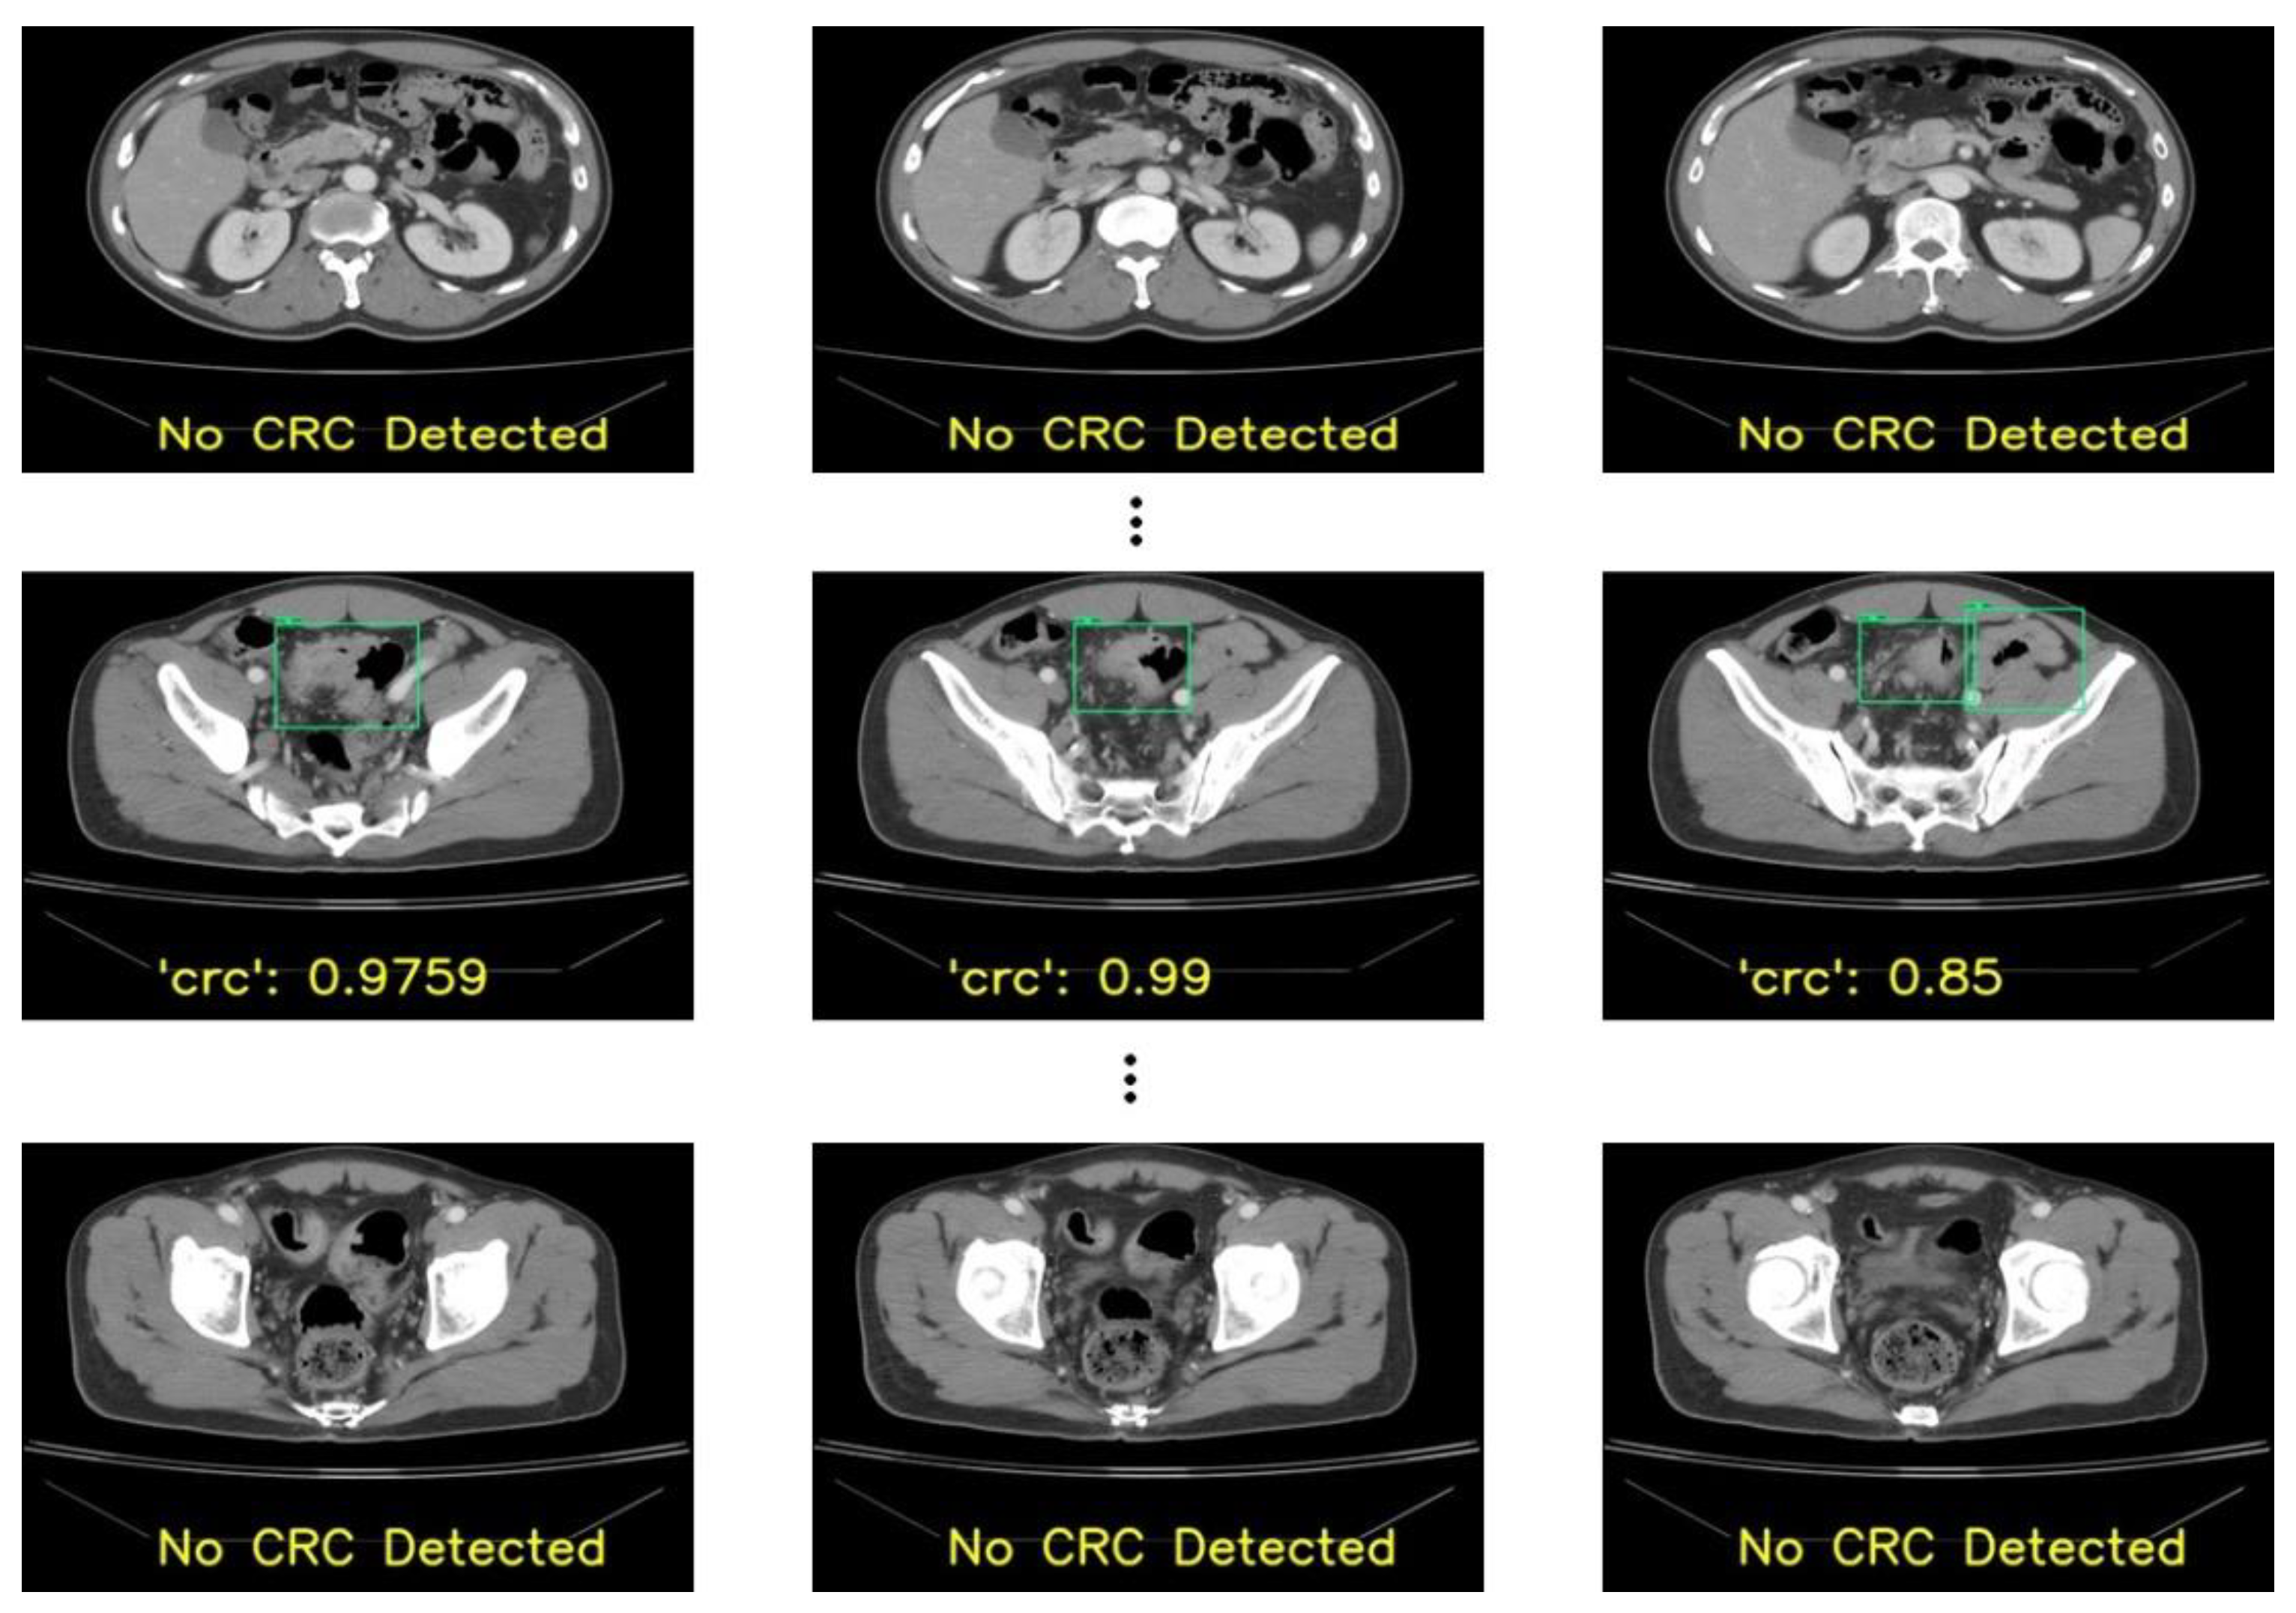

In addition to performing slice-wise testing, we used 42 patients’ data collected separately to perform patient-wise evaluation. The slices obtained from this set were preprocessed using the methods employed to preprocess the previously collected 190 patients’ data. After preprocessing, all the patients’ slices were fed to the derived localization model, and the outputs produced by the AI-based models were later verified by the experts. In our analysis, if the model could detect a lesion in 70% of a patient’s total positive slices, we considered the patient had a correct detection of CRC. Based on the observations, in our RetinaNet model, 67% of patients (28 out of 42) had correct localizations in more than 70% of slices. YOLOv3 performed similarly to RetinaNet with 67% of patients having correct localizations in more than 70% of slices. However, there were higher false positives (wrong localizations) found in the case of YOLOv3. Meanwhile, 31 patients had correct localizations in more than 70% of slices in the case of YOLOv8, with fewer false positives in comparison with the previous models. The models’ overall performances are recorded in Table 3, where a true positive represents a localization in the correct place, a true negative represents the number of slices with no CRC, FP represents the localization of CRC in either the wrong slice or location, and FN represents missing CRC in any slice. We considered a patient’s sensitivity as 1.00 if the proportion of slices with correct localization was 70% or higher.

Despite the tortuous structure of the colon, our proposed model—YOLOv8 with hyperparameter tuning—could detect CRC with very few false positives. Some outputs produced for one patient are shown in Figure 7. In addition, although some benign lesions were wrongly detected as CRC, as shown in Figure 7 in the second-row third image, the radiologists could focus on such lesions to examine the bowel wall thickening pattern and discard the lesion as CRC. In this way, the derived model can assist radiologists in the early diagnosis of CRC. In addition, clinicians can ask such patients to have follow-ups at regular intervals. With the assistance of the derived model, the number of CRC cases and morbidity due to late detection can be decreased.

Figure 7. Patient-wise testing showing CRC lesions localized (green box) with confident scores that were verified as the correct localization.